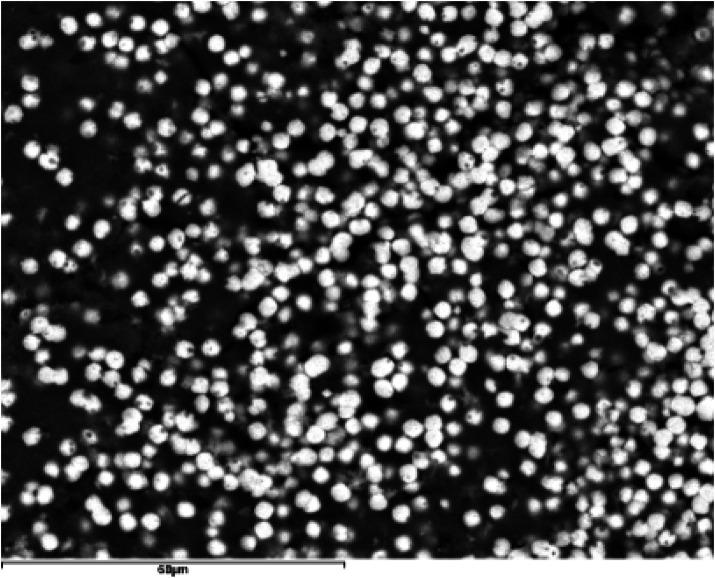

Salivary stones, or sialoliths, are calcified concretions forming within salivary glands and their ducts through a two-stage process: an initial formation of a central core via precipitation of inorganic material mediated by organic substances, followed by layering of additional organic and inorganic material. Substrates for sialolith formation include mucoid agglomerates, organic vesicles, foreign bodies, and bacterial biofilms. Understanding the detailed structure of sialoliths may aid in developing specific preventive or therapeutic strategies.

Most sialoliths were from the submandibular gland (82%), with the remainder from the parotid gland (18%). Parotid stones predominantly exhibited irregular shapes, while submandibular stones were generally ellipsoidal. All stones demonstrated an oolitic structure characterized by a central core surrounded by concentric layers and frequently associated with bacteria. Mineral composition predominantly included octacalcium phosphate (OCP), hydroxyapatite, and whitlockite. Larger sialoliths exhibited a higher proportion of hydroxyapatite, indicating increased crystallinity compared to OCP.

Despite diverse origins and locations, sialoliths share common morphological and compositional traits. Their formation begins with heterogeneous nucleation of calcium phosphates around organic spherules, likely induced by bacterial biofilms. These initial nuclei aggregate into a central core upon which additional layers of organic and inorganic materials deposit progressively. This layering increases the size and crystallinity of the sialoliths over time. The coexistence of amorphous phases and structural heterogeneity within layers explains the variability among stones. Detailed SEM-EDX analysis supports a unified conformational model for sialoliths that integrates the interplay of organic substrates, inorganic minerals, bacterial biofilms, and temporal factors.

涎石,即唾液腺结石,是在唾液腺及其导管内通过两个阶段形成的钙化凝块:首先通过有机物质介导的无机物质沉淀形成一个中心核,随后是额外的有机和无机物质分层堆积。涎石形成的底物包括黏液样聚集体、有机小泡、异物和细菌生物膜。了解涎石的详细结构可能有助于制定特定的预防或治疗策略。

大多数涎石来自下颌下腺(82%),其余来自腮腺(18%)。腮腺结石主要呈不规则形状,而下颌下结石通常为椭圆形。所有结石均表现出鲕状结构,其特征是有一个被同心层包围的中心核,且常与细菌相关。矿物质成分主要包括磷酸八钙(OCP)、羟基磷灰石和白磷钙矿。较大的涎石中羟基磷灰石的比例更高,表明与OCP相比结晶度增加。

尽管涎石的起源和位置各不相同,但它们具有共同的形态和成分特征。它们的形成始于围绕有机小球的磷酸钙异质成核,可能由细菌生物膜诱导。这些初始核聚集成一个中心核,在其上有机和无机材料的额外层逐渐沉积。随着时间的推移,这种分层增加了涎石的大小和结晶度。层内非晶相和结构异质性的共存解释了结石之间的变异性。详细的SEM-EDX分析支持了一个统一的涎石构象模型,该模型整合了有机底物、无机矿物质、细菌生物膜和时间因素之间的相互作用。